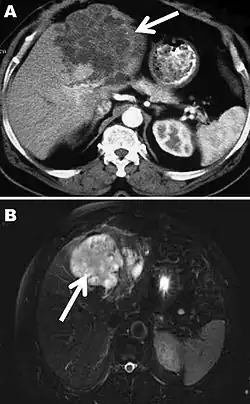

A) Computertomographie,

B) Magnetresonanztomographie

Weiterhin werden sowohl für die Diagnose als auch die Verlaufsbeurteilung einer alveolären Echinokokkose bildgebende Verfahren wie die Ultraschalluntersuchung, die Computertomographie und die Magnetresonanztomographie angewendet. Mit diesen Methoden ist allerdings nur eine Verlaufsbeobachtung der Krankheit erheblich zeitversetzt durch aufeinanderfolgende Untersuchungen zur Beurteilung der Größenveränderung parasitärer Schädigungen möglich. Leberschäden sind hingegen durch unterschiedliche Aktivität einzelner Bereiche charakterisiert, die etwa mit Hilfe von [18F]-Fluoro-Desoxyglukose-Positronen-Emissions-Tomographie (FDG-PET) bestimmt werden kann.[13]